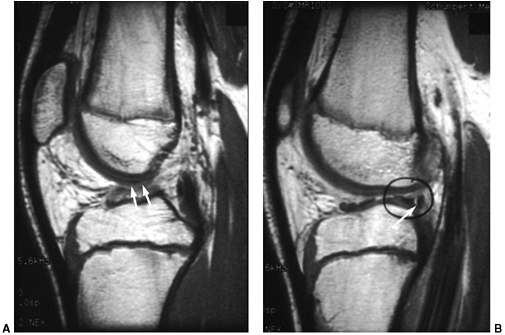

tears and osteochondral lesions, which may affect the decision

regarding surgery (Fig. 32.14 A,B). If the patient has clinical evidence of a torn ACL alone, an MRI is not indicated.

![]() |

|

Figure 32.14 Magnetic resonance imaging (MRI) of a skeletally immature individual with disruption of anterior cruciate ligament (white arrows) (A), and peripheral separation of lateral meniscus (white arrow and black circle) (B)